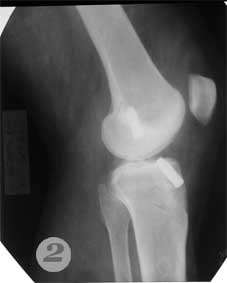

2,3 - после операции пластики передней крестовидной связки коленного сустава